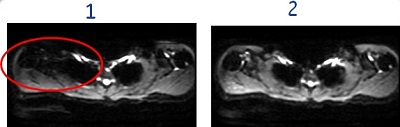

Figure 3. Real Time Center Frequency on/off affects on signal drop-off

Table 2. Image legend Number Description 1 Image acquired with Real Time Center Frequency option turned Off. The circle indicates the area of signal drop-off.

2 Image acquired with Real Time Center Frequency option turned On. Note the reduced signal drop-off.